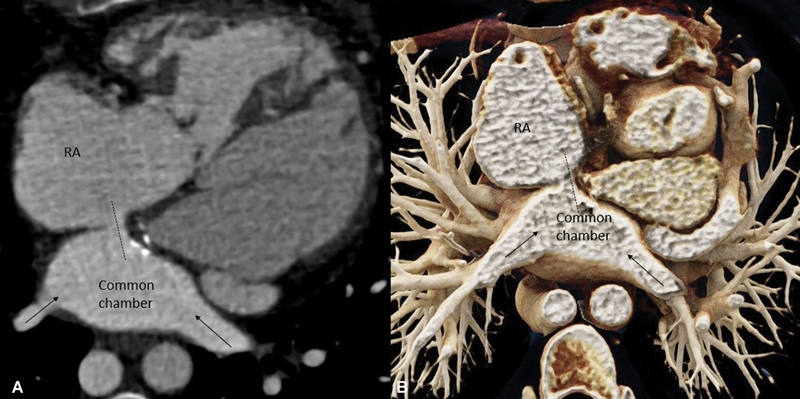

心房转换手术适用于大动脉转位患者。这种手术的并发症之一是造成挡板阻塞。我们描述了一个此类病例的计算机断层扫描结果,在该病例中,一名曾接受过大动脉转位房内修复手术的成人除了肺静脉引流受阻外,还延迟出现了复发性芥末挡板阻塞。

Atrial switch surgery is performed in patients with transposition of the great arteries. One of the complications of this surgery is obstruction of the baffle created. We describe the computed tomography findings of one such case where there was delayed presentation of recurrent Mustard baffle obstruction in addition to pulmonary venous drainage obstruction in an adult previously operated on for intra-atrial repair of transposition of the great arteries.